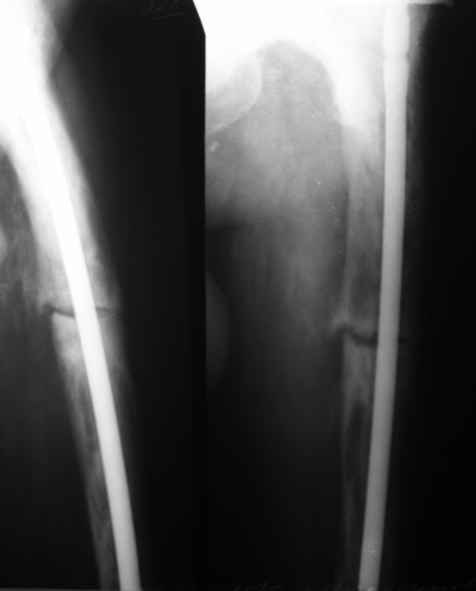

бывали ли у кого-нибудь такие случаи Уважаемые коллеги, вчера прооперировал женщину 60 лет с болезнью Педжета, переломом верхней трети бедра. Выявлена в августе этого года, сломала три дня назад от небольшого усилия. Из сопутствующих болезней лейкоз, сахарный диабет. Бывали ли кого-нибудь такие случаи, чем это все заканчивалось?